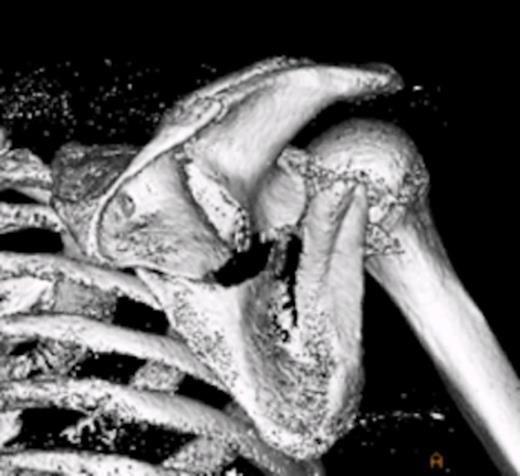

On examination there was restriction of the range of movement of the right shoulder with tenderness and swelling over the scapular. The skin was intact. There was no neurovascular deficit and the patient was otherwise physically well. X-rays revealed a fracture of the body of the scapula with posterior displacement of the inferior fragment. The shoulder joint was not dislocated and there were no associated fractures of the proximal humerus. The patient was admitted for analgesia and computed tomography was performed to assess the fracture. The scan showed involvement of the glenoid, with the fracture extending through the posterior lip. This was deemed inappropriate for surgical fixation. The patient was managed in a broad arm sling and discharged with simple range of movement exercises.

Computed tomographic scan, showing fracture extension into glenoid

Computed tomographic scan with 3D reconstruction showing the scapula fracture